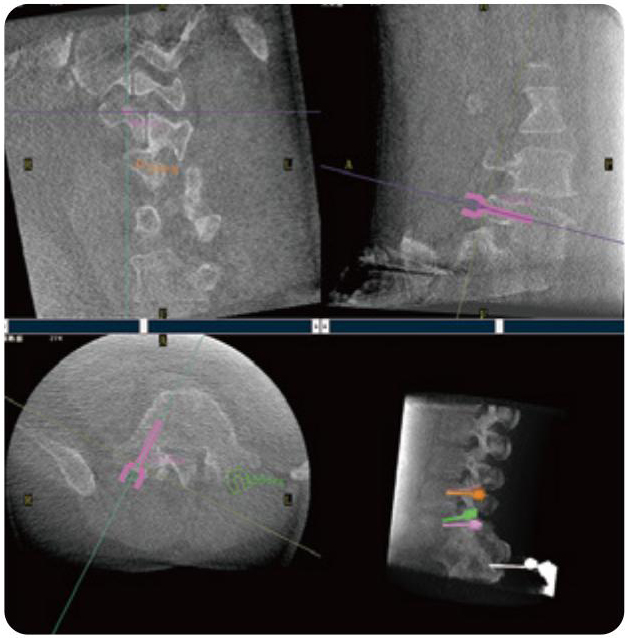

PL300B可應用于多節(jié)段脊柱外科手術,輔助醫(yī)生定位病灶部位,為脊柱外科手術(經(jīng)皮椎體成形術、椎弓根螺釘內(nèi)固定術等術式)提供術前手術流程規(guī)劃、入釘位置、角度可視化引導,模擬仿真入釘輔助。

PL300B搭配普愛醫(yī)療自主研發(fā)生產(chǎn)的平板3D C形臂,借助一體化自適應配準( 軌跡配準)技術,通過追蹤C形臂三維采集軌跡,自動完成圖像坐標建立和系統(tǒng)坐標配準。配準精度更高,操作步驟少,系統(tǒng)運作效率高。